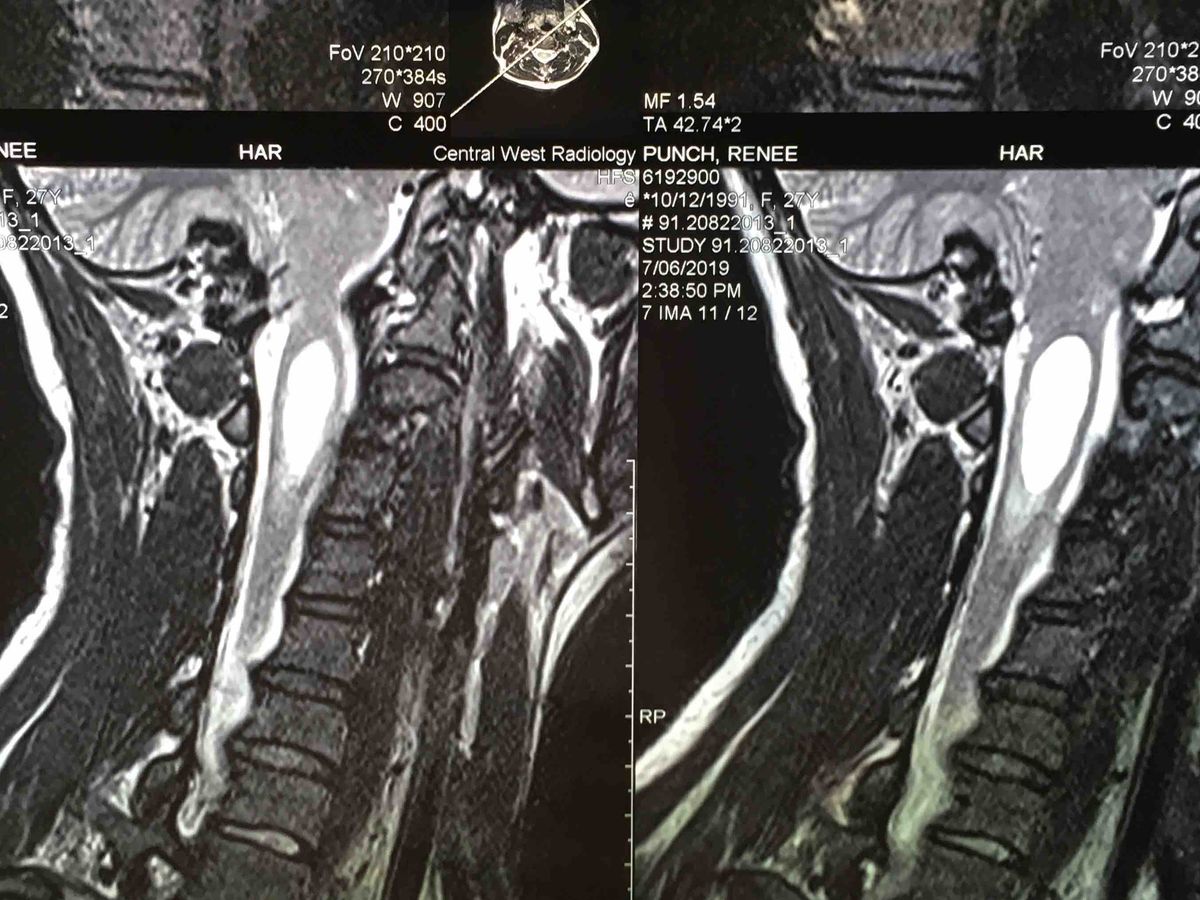

My partner Renee is being rushed in for emergency surgery in Sydney. She is having Suboccipital Craniectomy and a Patch Graft for her Chiari Malformation and Syrinx decompression. We have recently found out that it has grown rather rapidly which can cause quadriplegia if she doesn’t have the surgery done. Unfortunately as it is in such a short time period we don’t have the money to pay for the surgery and we need your help. The specialists themselves is going to cost $6000, then we have the MRI which is another $800 and also the anaesthetists will apparently have additional fees which we have been told are $3150 and only 30% is covered by health care.